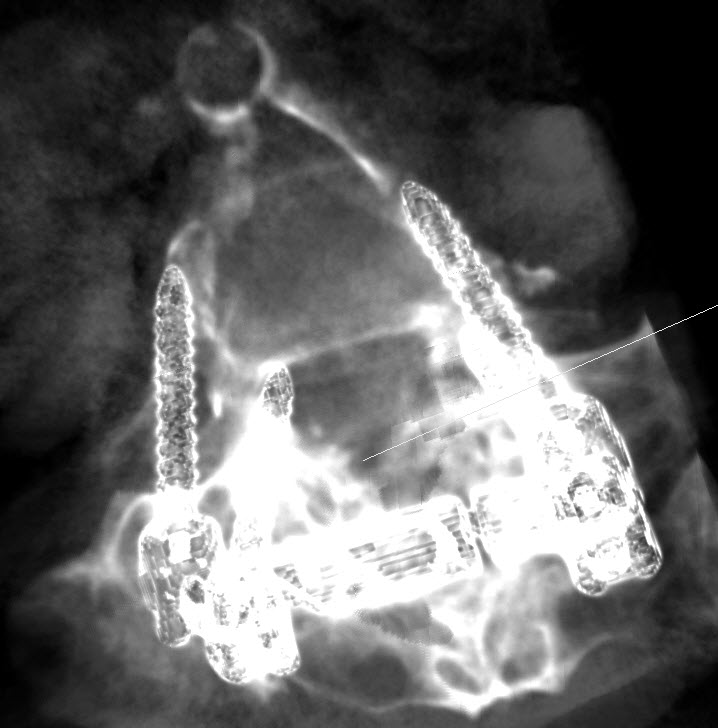

17-JANUARY-2021  HUDA AHMAD DAASAN  57 YEARS  UNACCEPTABLE UPPER SCREWS LOCATION AFTER FIXATION DONE 3 DAYS AGO.

The patient power of the lower limbs improved, but she is telling that the right gastrocnemius muscle is tight. Control CT-scan of the constructs performed the evening of 16-January-2021 showed unacceptable both upper screws at the level of L5. The sacral screws are acceptable. It was decided to explore the wound redirect the upper screws.

The left upper screw far-lateral.

The right upper screw far lateral and above the pedicle.

The upper screws are far lateral.

X-ray reconstruction using ORS Visual program

Post correction performed 18-January-2021